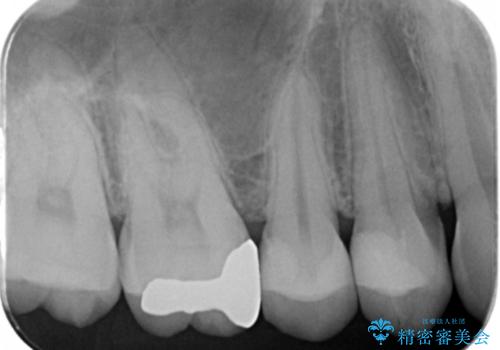

- 定期検診でレントゲンを撮影したところ虫歯があったので拡大鏡下で虫歯を取り除き、白い詰め物にて治療しました。

無事歯の神経を取らずに白い詰め物で治療する事ができました。

歯がズキズキ痛くなるという現象は歯の神経にまで虫歯が進行し歯髄炎になっている可能性が高く、神経を取らなければならなくなってしまいます。